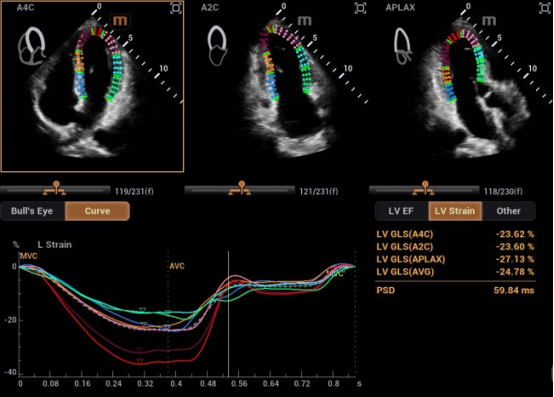

在研发中,迈瑞研发团队另辟蹊径,推出了自动左心室应变评估 Auto Strain LV 。该功能不再依赖心电信号作为"时间坐标",而是让AI直接识别心脏机械运动的关键节点------当二尖瓣关闭、主动脉瓣开放,这些瓣膜运动的瞬间,就是心脏收缩与舒张的自然锚点。

自动左心室应变评估 Auto Strain LV(非心电触发)

迈瑞也在与尹立雪教授团队牵头的合作项目中,挖掘出自动左心室应变评估 Auto Strain LV 更多的临床应用价值,成功让心肌应变检测技术摆脱"心电图(ECG)"的束缚。尹教授表示:"基于人工智能的图像技术,现在已实现无需同步心电图的自动心肌应变分析。该技术操作便捷,检测结果与传统方法高度一致,且能早于传统指标识别心肌功能异常,为疾病早期干预提供关键支撑。"